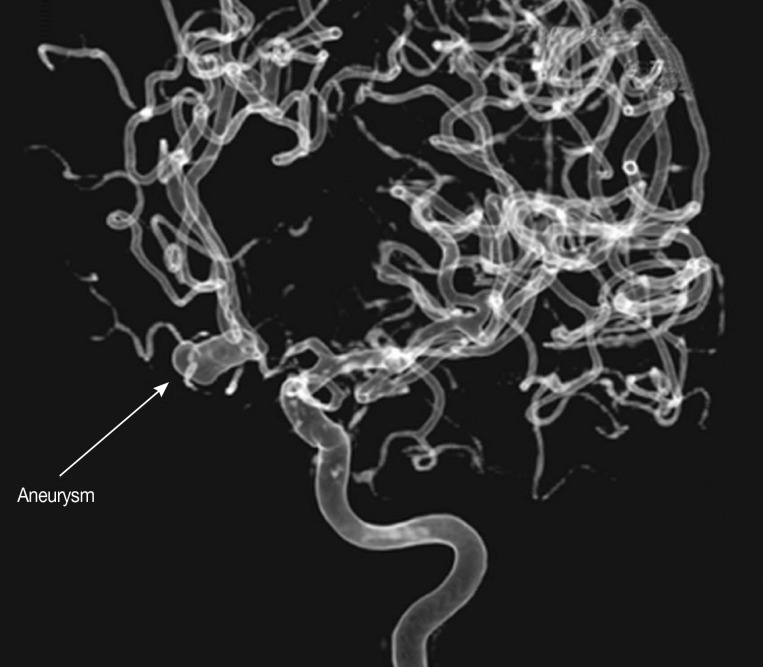

Fig. 1) or MR imaging of the brain were available, 2) results of CT angiography (CTA) or MR angiography (MRA) or 3-dimensional digital subtraction cerebral angiography (DSA) were available (

Fig. 2) to identify any intracranial aneurysm that might be present (

Fig. 3), and 3) results of immunoblot analysis for antibodies against 21-or 24-kDa antigen band of

All eligible patients were categorized into 2 groups; aneurysmal SAH (A-SAH) and non-aneurysmal SAH (NA-SAH). The former group included those SAH patients with intracranial aneurysm detected by CTA and/or MRA and/or DSA. The technique and procedures of DSA have been described elsewhere [

Fig. 3Three-dimensional digital subtraction cerebral angiography (DSA), lateral view of internal carotid artery and anterior cerebral artery showing subarachnoid hemorrhage from aneurysm at anterior communicating artery.